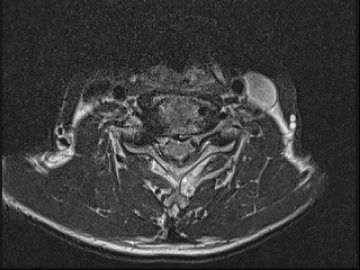

2022.08.11

2022.08.16

ㆍ환자 동의를 받은 자료이며, 이미지 사진은 실물과 다를 수 있습니다.

ㆍ모든 자료는 새움병원 자료입니다.